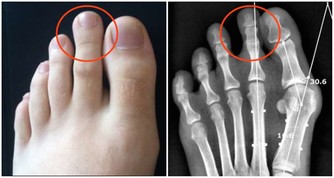

9.會引起頸椎僵硬: 久坐會影響頸動脈對頭部的供血,還破壞了正常生理彎曲,容易出現弓背或骨質增生。